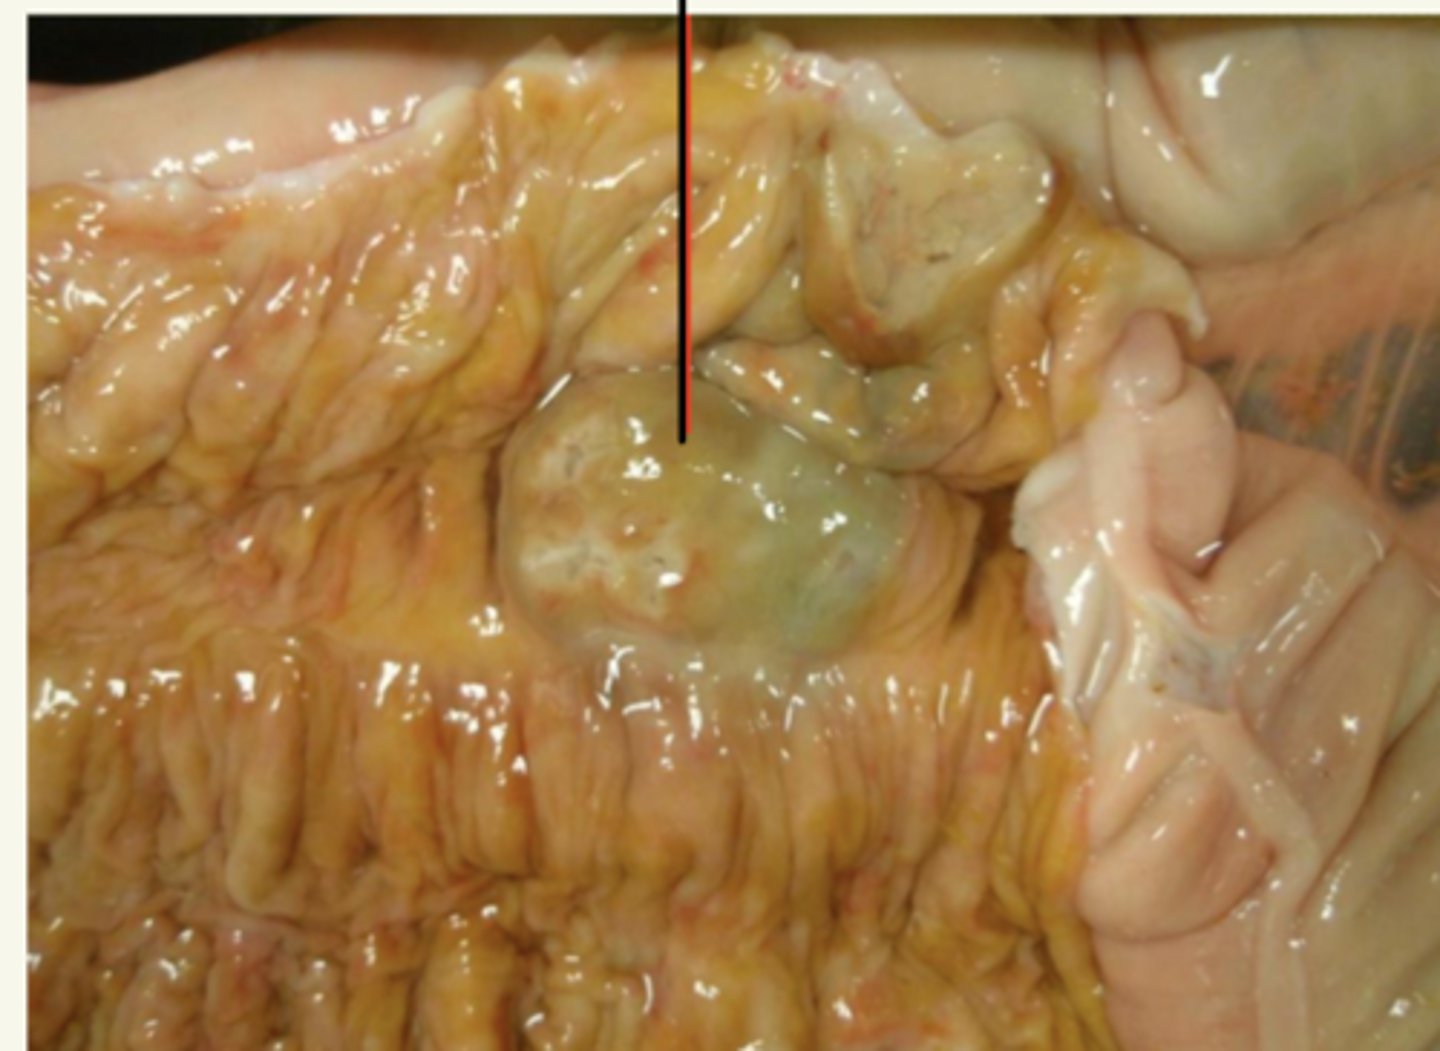

enteritis, por Salmonella (botones pestosos- típicos de salmonella)

¿patología morfológica y etológica?

enteritis necrótico-fibrinosa

(por salmonella)

¿patología morfológica?